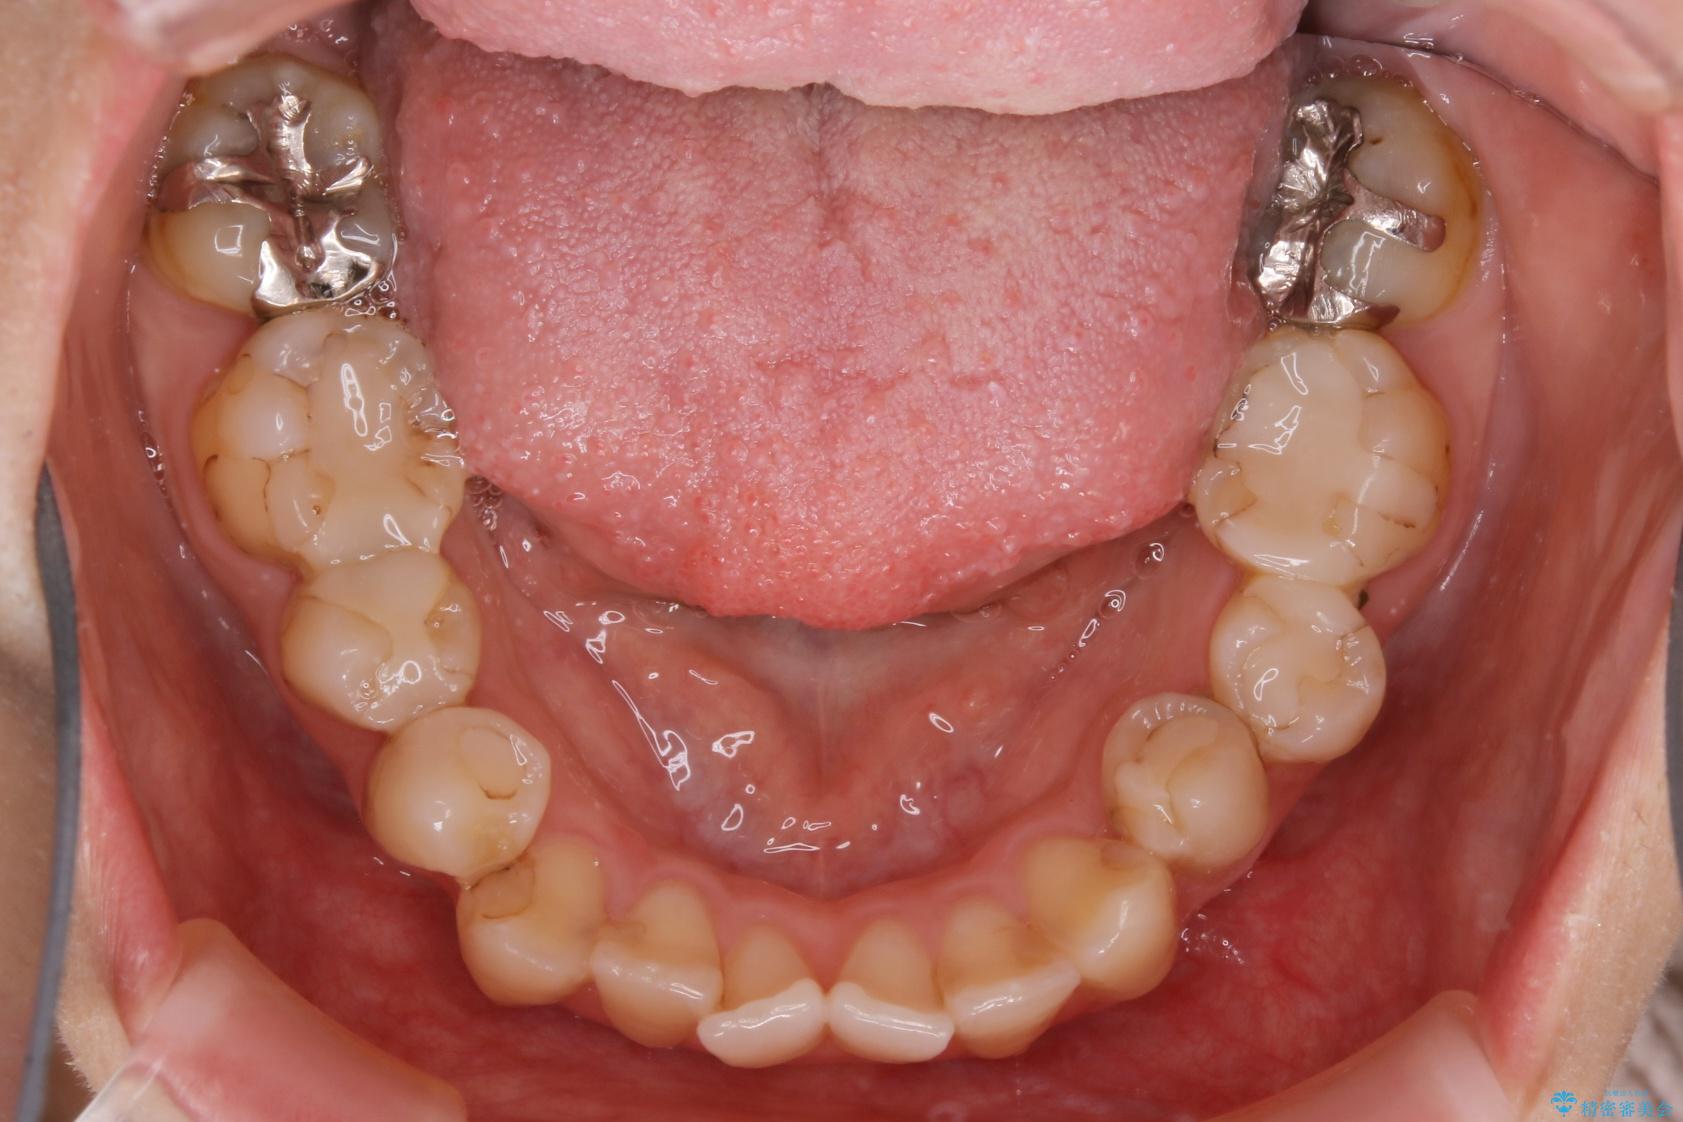

治療前

20代 女性 非抜歯で歯列をコンパクトに20代 女性 非抜歯で歯列をコンパクトに20代 女性 非抜歯で歯列をコンパクトに